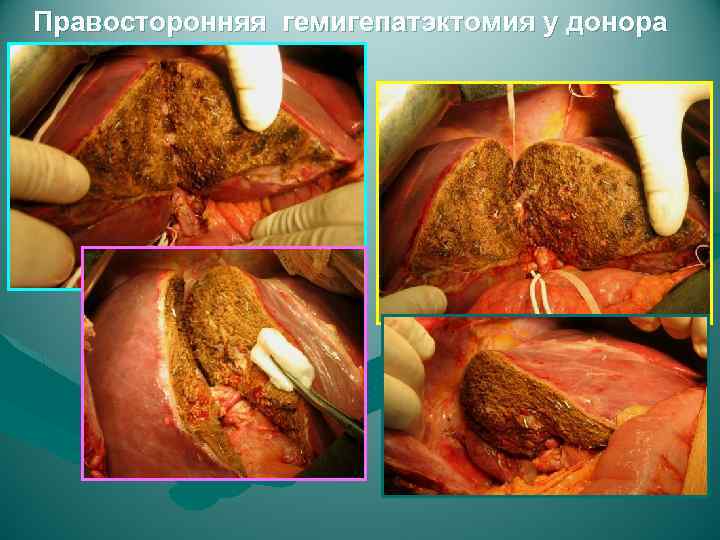

Правосторонняя гемигепатэктомия у донора

Правосторонняя гемигепатэктомия у донора

Правосторонняя гемигепатэктомия у донора

Правосторонняя гемигепатэктомия у донора